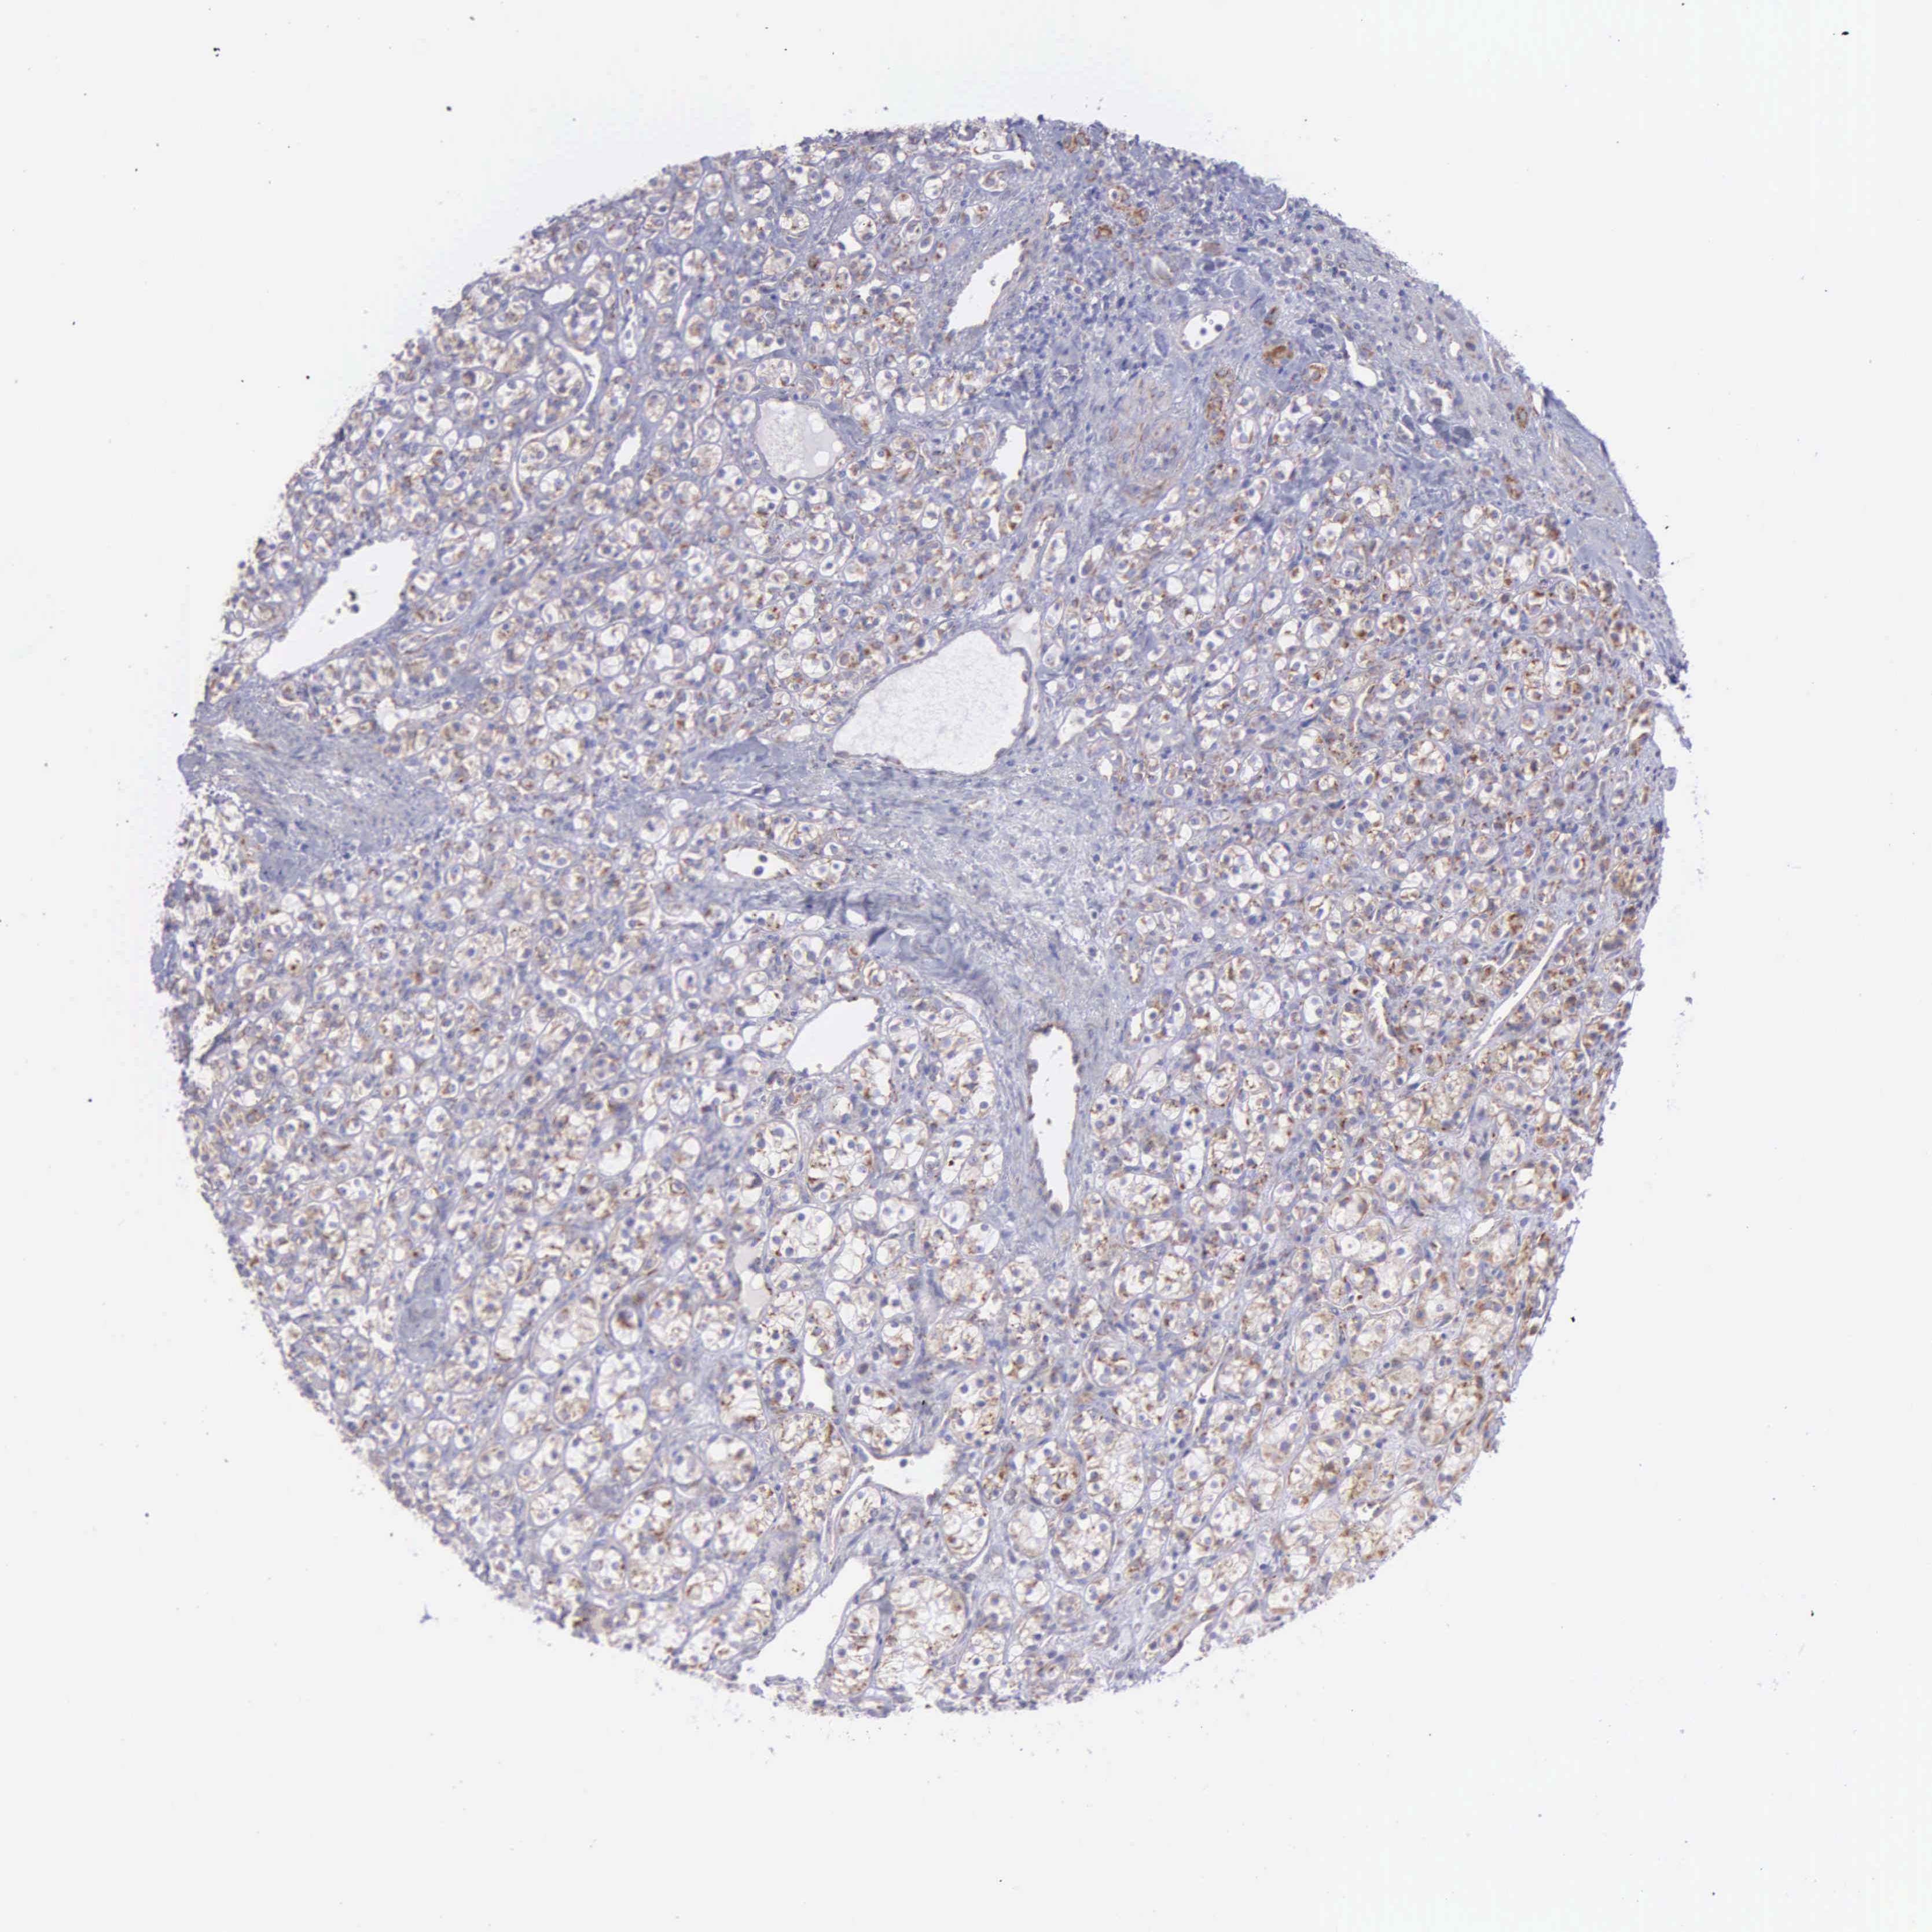

KIDNEY RENAL CLEAR CELL CARCINOMA (TCGA) - Interactive survival scatter ploti

The Survival Scatter plot shows the clinical status (i.e. dead or alive) for all individuals in the patient cohort, based on the same data that underlies the corresponding Kaplan-Meier plots. Patients that are alive at last time for follow-up are shown in blue and patients who have died during the study are shown in red.

The x-axis shows the expression levels (FPKM) of the investigated gene in the tumor tissue at the time of diagnosis. The y-axis shows the follow-up time after diagnosis (years). Both axes are complimented with kernel density curves demonstrating the data density over the axes. The top density plot shows the expression levels (FPKM) distribution among dead (red) and alive patients (blue). The right density plot shows the data density of the survived years of dead patients with high and low expression levels respectively, stratified using the cutoff indicated by the vertical dashed line through the Survival Scatter plot. This cutoff is automatically defined based on the FPKM cutoff that minimizes the p-score. The cutoff can be changed by dragging the vertical line or by entering a cutoff value in the square labeled "Current cut-off".

Under the Survival Scatter plot the p-score landscape (black curve; left axis) is shown together with dead median separation (red curve; right axis). Dead median separation is the difference in median mRNA expression between patients who have died with high and low expression, respectively. It is calculated as follows: median FPKM expression of dead patients with high expression - median FPKM expression of dead patients with low expression. This is intended to aid the user in visually exploring custom cutoffs and the associated p-scores and dead median separation.

Individual patient data is displayed and can be filtered by clicking on one or more of the category buttons on the top of the page. Categories describing expression level and patient information include: high, low, alive, dead, female, male and tumor stages. The scale of the x-axis can be toggled between linear and log-scale by clicking on the "x log" button. Mouse-over function shows TCGA ID, patient information and mRNA expression (FPKM) for each patient.

& Survival analysisi

Kaplan-Meier plots summarize results from analysis of correlation between mRNA expression level and patient survival. Patients were divided based on level of expression into one of the two groups "low" (under cut off) or "high" (over cut off). X-axis shows time for survival (years) and y-axis shows the probability of survival, where 1.0 corresponds to 100 percent.

SYNJ2BP is validated prognostic, high expression is favorable in Kidney Renal Clear Cell Carcinoma (TCGA)

Best expression cut offi

Based on the FPKM value of each gene, patients were classified into two groups and association between prognosis (survival) and gene expression (FPKM) was examined. The best expression cut-off refers the FPKM value that yields maximal difference with regard to survival between the two groups at the lowest log-rank P-value. Best expression cut-off was selected based on survival analysis .

When clicking on this number, the vertical dashed line indicating cut-off, the interactive survival plot, and the Kaplan-Meier curve will be adjusted to show results based on the best expression cut-off.

: 9.68

TCGA RNA samplesi

RNA-seq data is reported as average FPKM (number Fragments Per Kilobase of exon per Million reads), generated by the The Cancer Genome Atlas (TCGA) .

Normal distribution across the dataset is visualized with box plots, shown as median and 25th and 75th percentiles. Points are displayed as outliers if they are above or below 1.5 times the interquartile range. FPKM values of the individual samples are presented next to the box plot.

Average pTPM 10.6

Number of samples 521